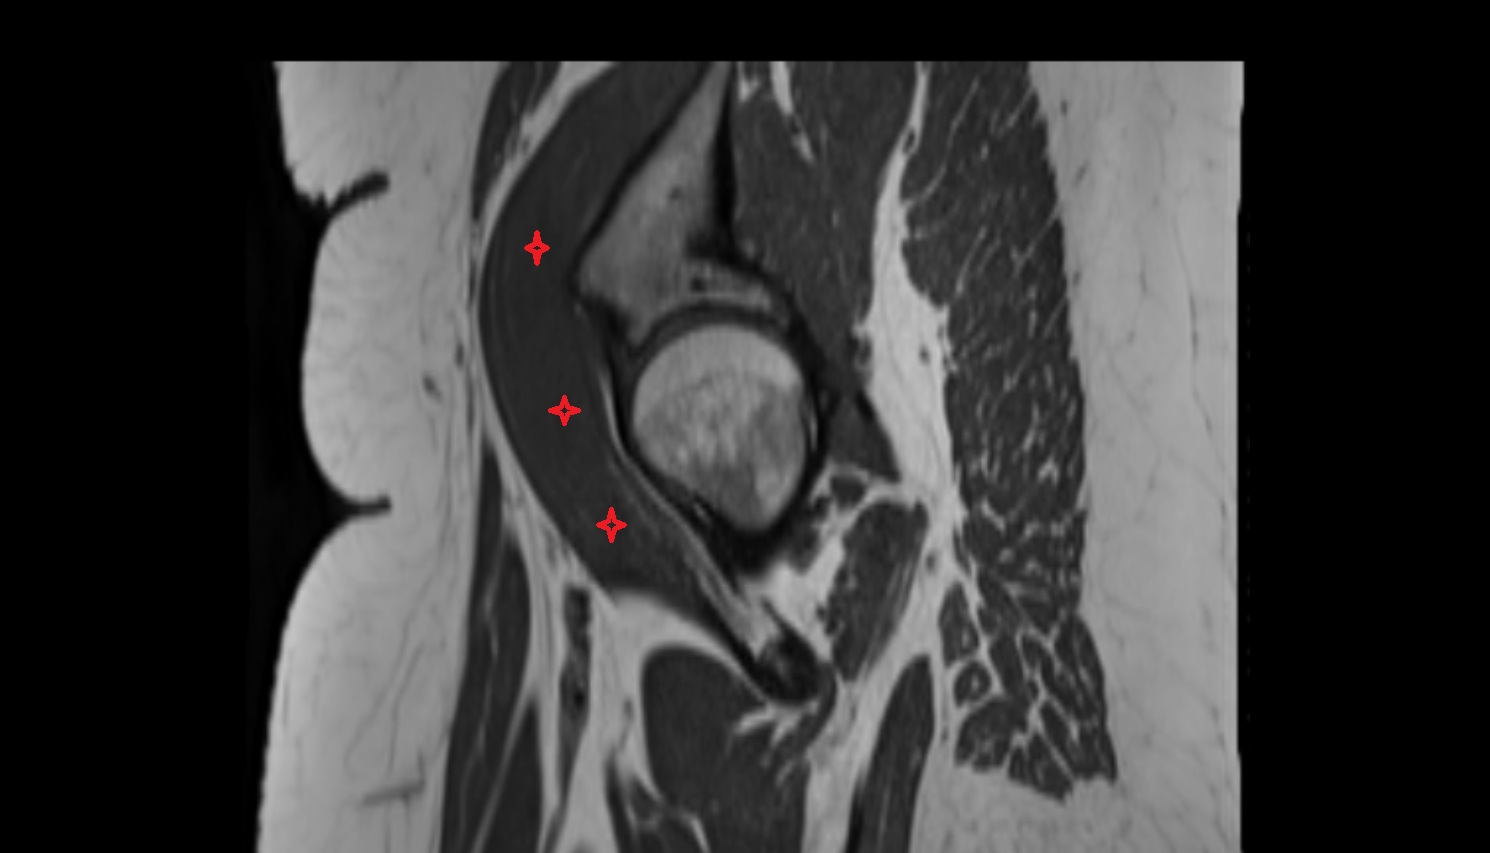

- Subacromial space